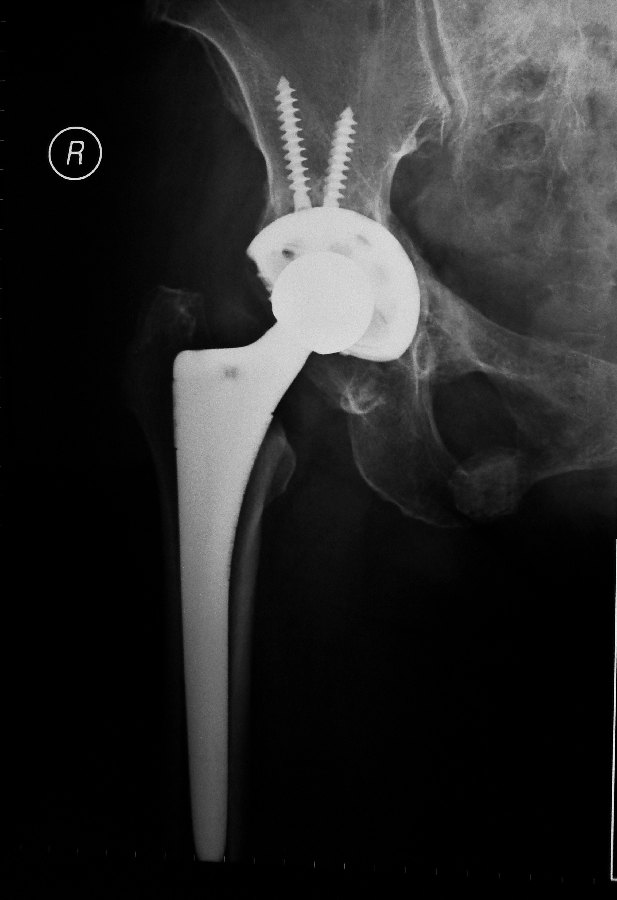

This surgery removes the arthritic part of the joint and replacing it with metal cup and metal head. A plastic cup is inserted into the metal cup and this allows the metal head to articulate with the plastic within the metal cup.

This is the post-operative x-rays showing the hip implants:

The patient usually will be able to get up to walk with a walking frame either on the 1st or 2nd day after the surgery.